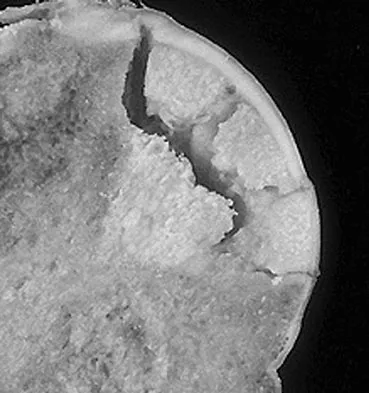

A 14-year-old boy reports progressive right wrist pain. Radiographs are shown in Figure 3a, and a photomicrograph is shown in Figure 3b. What is the most likely diagnosis?

The radiographs show a benign-appearing, well-defined lytic lesion with a thin rim of surrounding reactive bone. The photomicrograph shows spindle cells with a myxoid cartilaginous matrix. These findings are diagnostic of chondromyxoid fibroma. This is a rare, benign tumor that usually causes pain and can be locally aggressive. Lersundi A, Mankin HJ, Mourikis A, et al: Chondromyxoid fibroma: A rarely encountered and puzzling tumor. Clin Orthop Relat Res 2005;439:171-175.